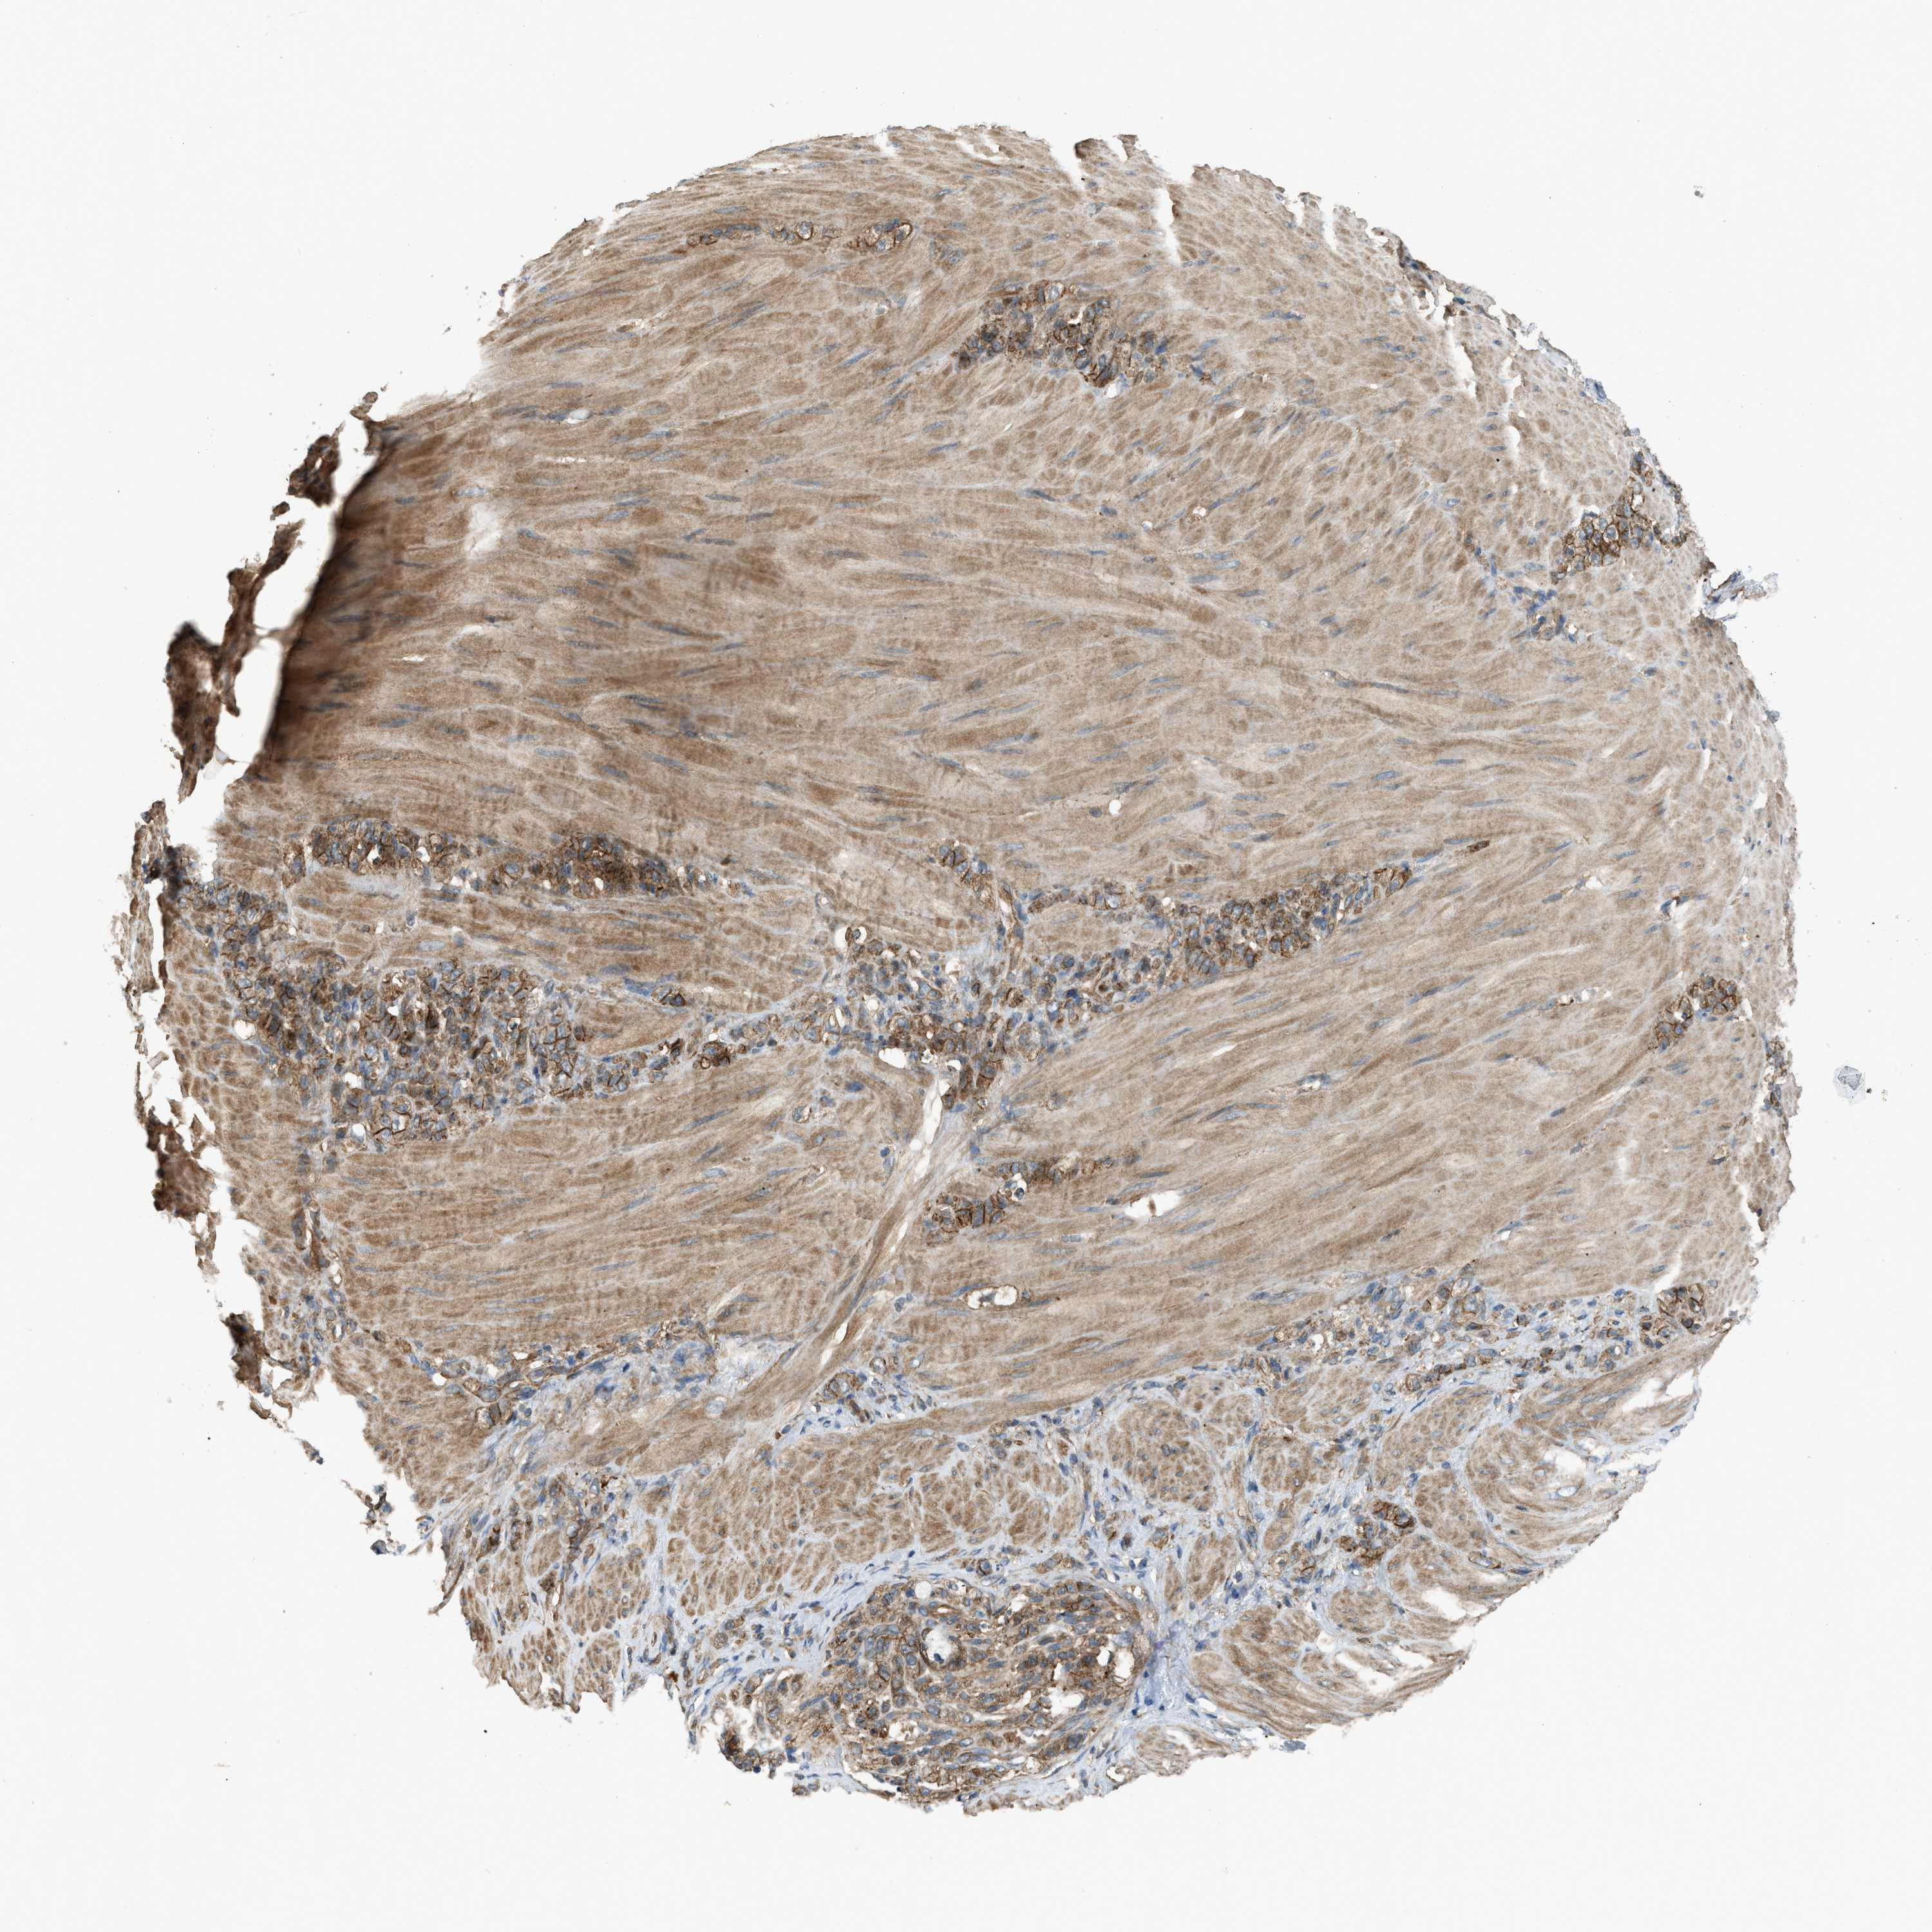

STOMACH CANCER - Protein expressioni

A mouse-over function shows sample information and annotation data. Click on an image to view it in a full screen mode. Samples can be filtered based on level of antibody staining by selecting one or several of the following categories: high, medium, low and not detected. The assay and annotation is described here.

Note that samples used for immunohistochemistry by the Human Protein Atlas do not correspond to samples in the TCGA dataset.

Antibody stainingi

Antibody staining in the annotated cell types in the current human tissue is reported as not detected, low, medium, or high, based on conventional immunohistochemistry profiling in selected tissues. This score is based on the combination of the staining intensity and fraction of stained cells.

Each image is clickable and will lead to virtual microscopy that enables deeper exploration of all samples and also displays staining intensity scores, fraction scores and subcellular localization as well as patient and tissue information for each sample.

Antibody HPA018951

Antibody CAB013716

Staining

High

Medium

Low

Not detected

Intensity

Strong

Moderate

Weak

Negative

Quantity

>75%

75%-25%

<25%

None

Location

Nuclear

Cytoplasmic/membranous

Cytoplasmic/membranous,nuclear

Adenocarcinoma, NOS

Adenocarcinoma, High grade